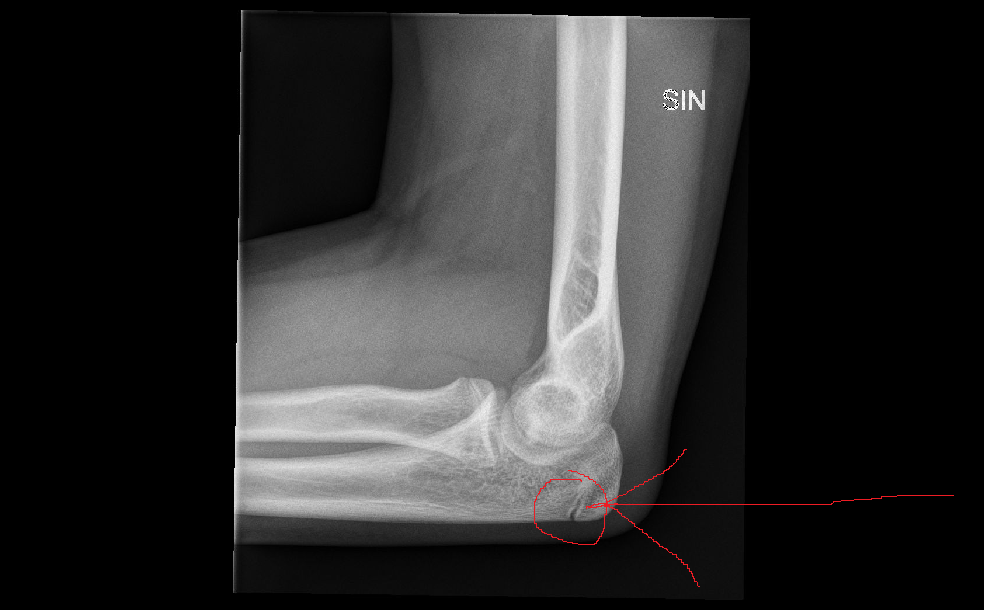

Оссификаты Локтевого Сустава: Диагностика и Лечение

Раздел: Секреты мастерства